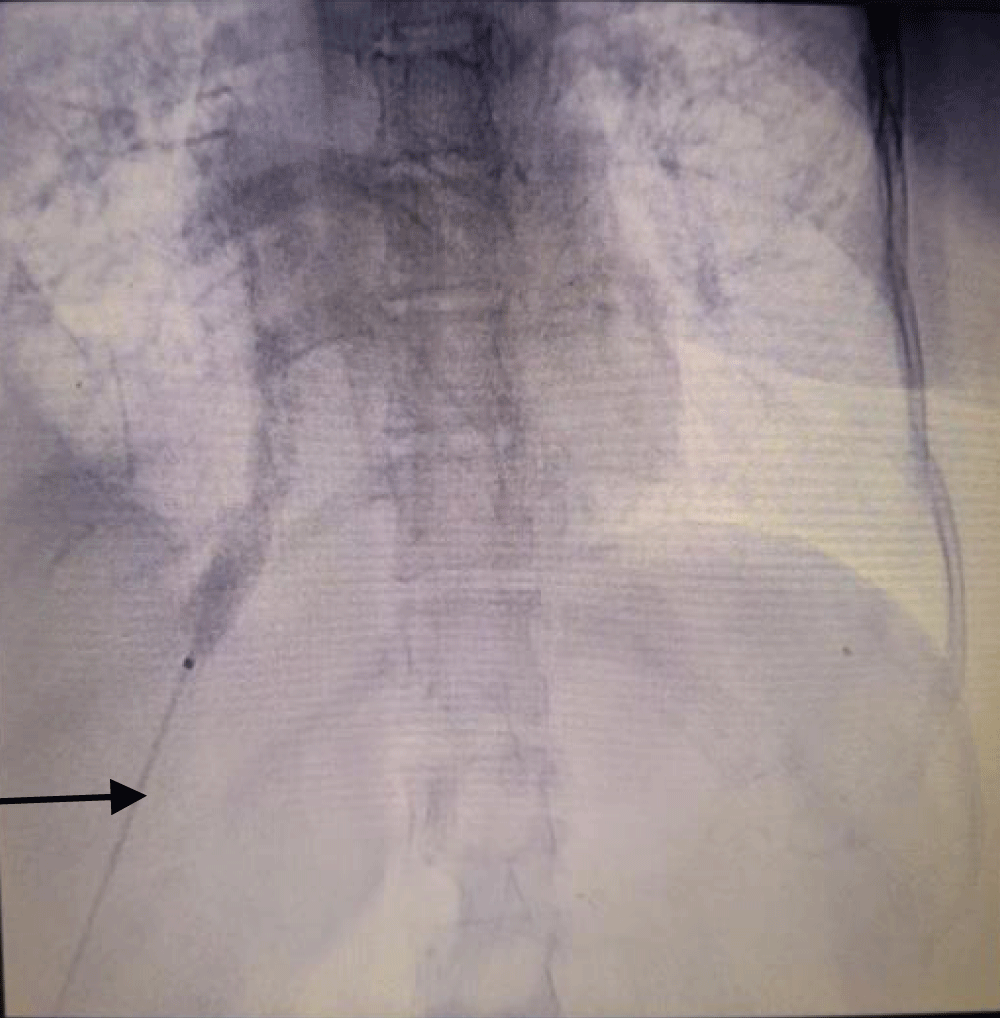

The patient was taken to the cath lab where the procedure was done under ultrasound and fluoroscopy guidance. The procedure was done with a sterile technique and using anti-septic measures; in the cath lab. After cleaning and draping the abdomen, first the right hepatic vein was visualized via ultrasound, and it was punctured by a Chiba needle via the percutaneous route. A guide wire was passed and its position was traced by ultrasound (Figure 1) and fluoroscopy (Figure 2). Radial artery sheath and Kumpe catheter were used as needed to negotiate guide wire in the inferior vena cava and right atrium. A subcutaneous tunnel of 5 cm was created and a tunnelled dialysis catheter was pulled through it (Figure 3). Contrast was injected into the sheath to visualize its flow. The contrast was seen flowing in the right atrium confirming the correct position of the sheath and the kumpe wire (Figure 4). The guide wire was then reinserted into the sheath. As the guide wire reached the inferior vena cava, it was negotiated to the right atrium. This was followed by the removal of the sheath and kumpe wire. After confirming the position of the guide wire in the right atrium (Figure 2), sequential dialation of the tract was done by dilators 6 fr, 8 fr, 10 fr, 12 fr, 14 fr, and finally 14.5 Fr x 19 cm trans-hepatic tunneled dialysis catheter was secured along with subcutaneous tunnel (Figures 5,6). The catheter tip was kept at the junction of the right atria – inferior vena cava (Figure 5). Ultrasound of the liver was done to rule out haemorrhage. There was slight post-operative pain post catheter insertion which subsided after a while. She was kept in the intensive care unit for a day for monitoring of vitals and was moved to the ward the next day. The procedure was uneventful. After being discharged, the patient underwent multiple sessions of hemodialysis with this access. She was told to take proper hygiene care of the area where the catheter was inserted to prevent catheter-related bloodstream infections. She once had an upper respiratory tract infection following which she had poor flow from the tunneled trans-hepatic dialysis catheter. She underwent repositioning of the catheter in the cath lab following which good flow was achieved. She was explained to avoid forceful coughing which can displace the catheter from its position; hampering the flow.

Figure 2: Fluoroscopy image of guide wire (arrow pointing at it) being negotiated from right hepatic vein to inferior vena cava and finally to right atrium.